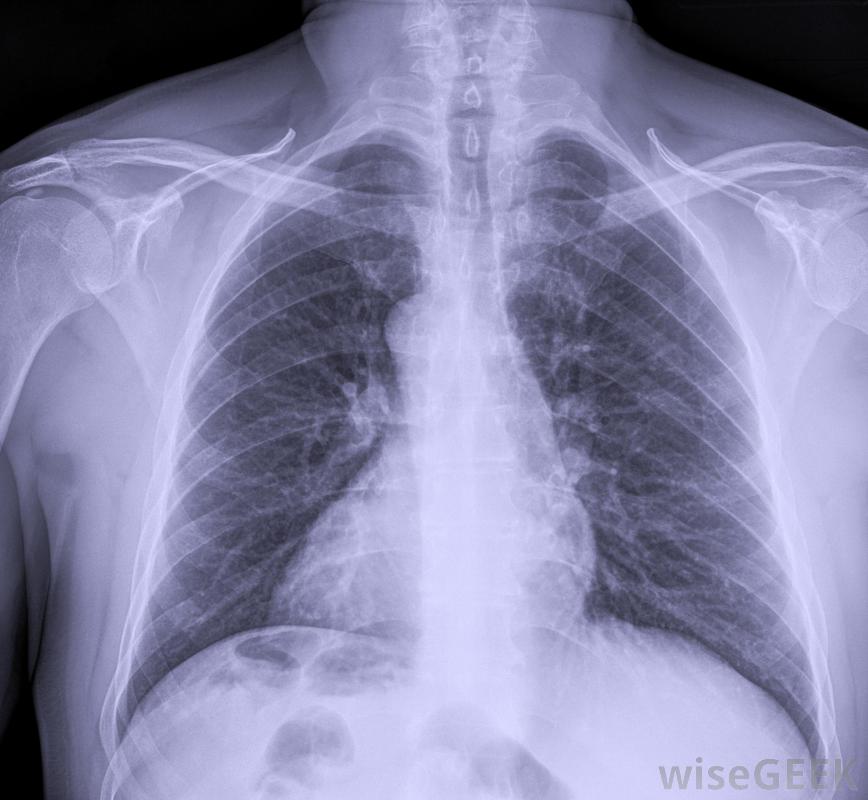

胸膜纤维化影响覆盖肺部的组织胸膜纤维化有多种原因,通常与石棉暴露有关,病理学家在严重情况下对胸膜进行解剖时,常常发现胸膜中嵌入石棉纤维,有时长达15年,也可能是由炎症过程、手术创伤或胸腔积液引起的。在轻度病例中,这种情况会导致小面积的纤维组织发育,这可能不会给患者带来任何问题,并且在胸部x光片上也会发现与此无关的原因

将检查胸部X光片是否有胸膜纤维化的迹象当胸膜严重时,整个肺组织会变得很致密,像是很容易膨胀的白色组织当胸膜增厚时,肺不得不更加努力地充气,最终增厚的组织会损害肺功能,使病人无法呼吸或呼吸极度困难。在这种情况下,受损的胸膜必须手术切除,这样肺部才能充气

即使是轻度病例,也经常建议进行活检,以确认生长是良性的,而不是癌症。病情严重的病人会因为呼吸困难而寻求治疗。医生可以通过胸部x光片等工具来诊断病情,对可疑组织进行活检,并听肺部的声音。即使是轻微的病例,也经常建议进行活检,以确认肿瘤是良性的,而不是癌性的,因为癌症的治疗方法与胸膜纤维化的治疗方法大不相同